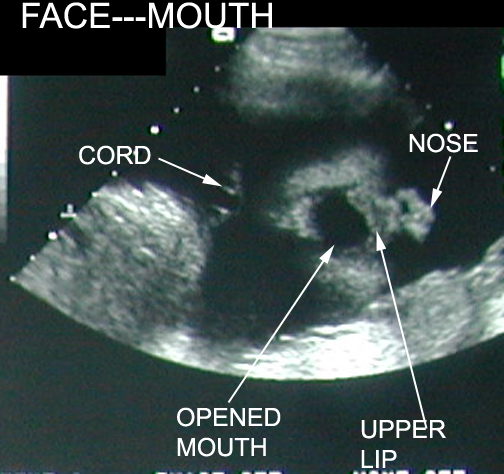

Face

Nose lips